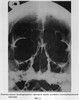

Предварительно для решения поставленной задачи было проведено рентгенологическое исследование, которое включало экспериментальный и клинический разделы. На этапе эксперимента для отработки оптимальной укладки с контрольной визуализацией получаемого рентгенографического изображения, ориентации центрального луча и соответствия ему анатомических образований лицевого скелета использовался скелетированный препарат черепа человека (фиг.2). Кроме того, подбирали оптимальный рентгенографический режим и параметры съемки.